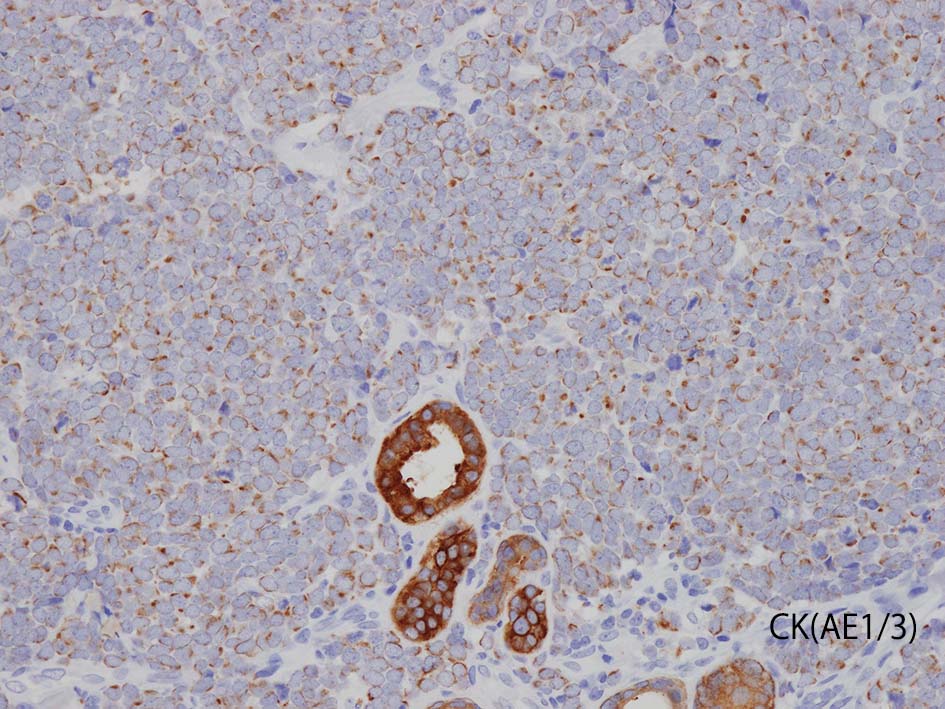

- 陽性上皮系マーカ; CAM5.2, AE1/3, CK20, BerEP4, EMA

CK(AE1/3); CK20は含まない, のほうがdot-likeな染まりをしている. CK20は膜にも陽性になっている. LCAは陰性. 神経内分泌マーカのchromograninA, synaptophysinは陽性.